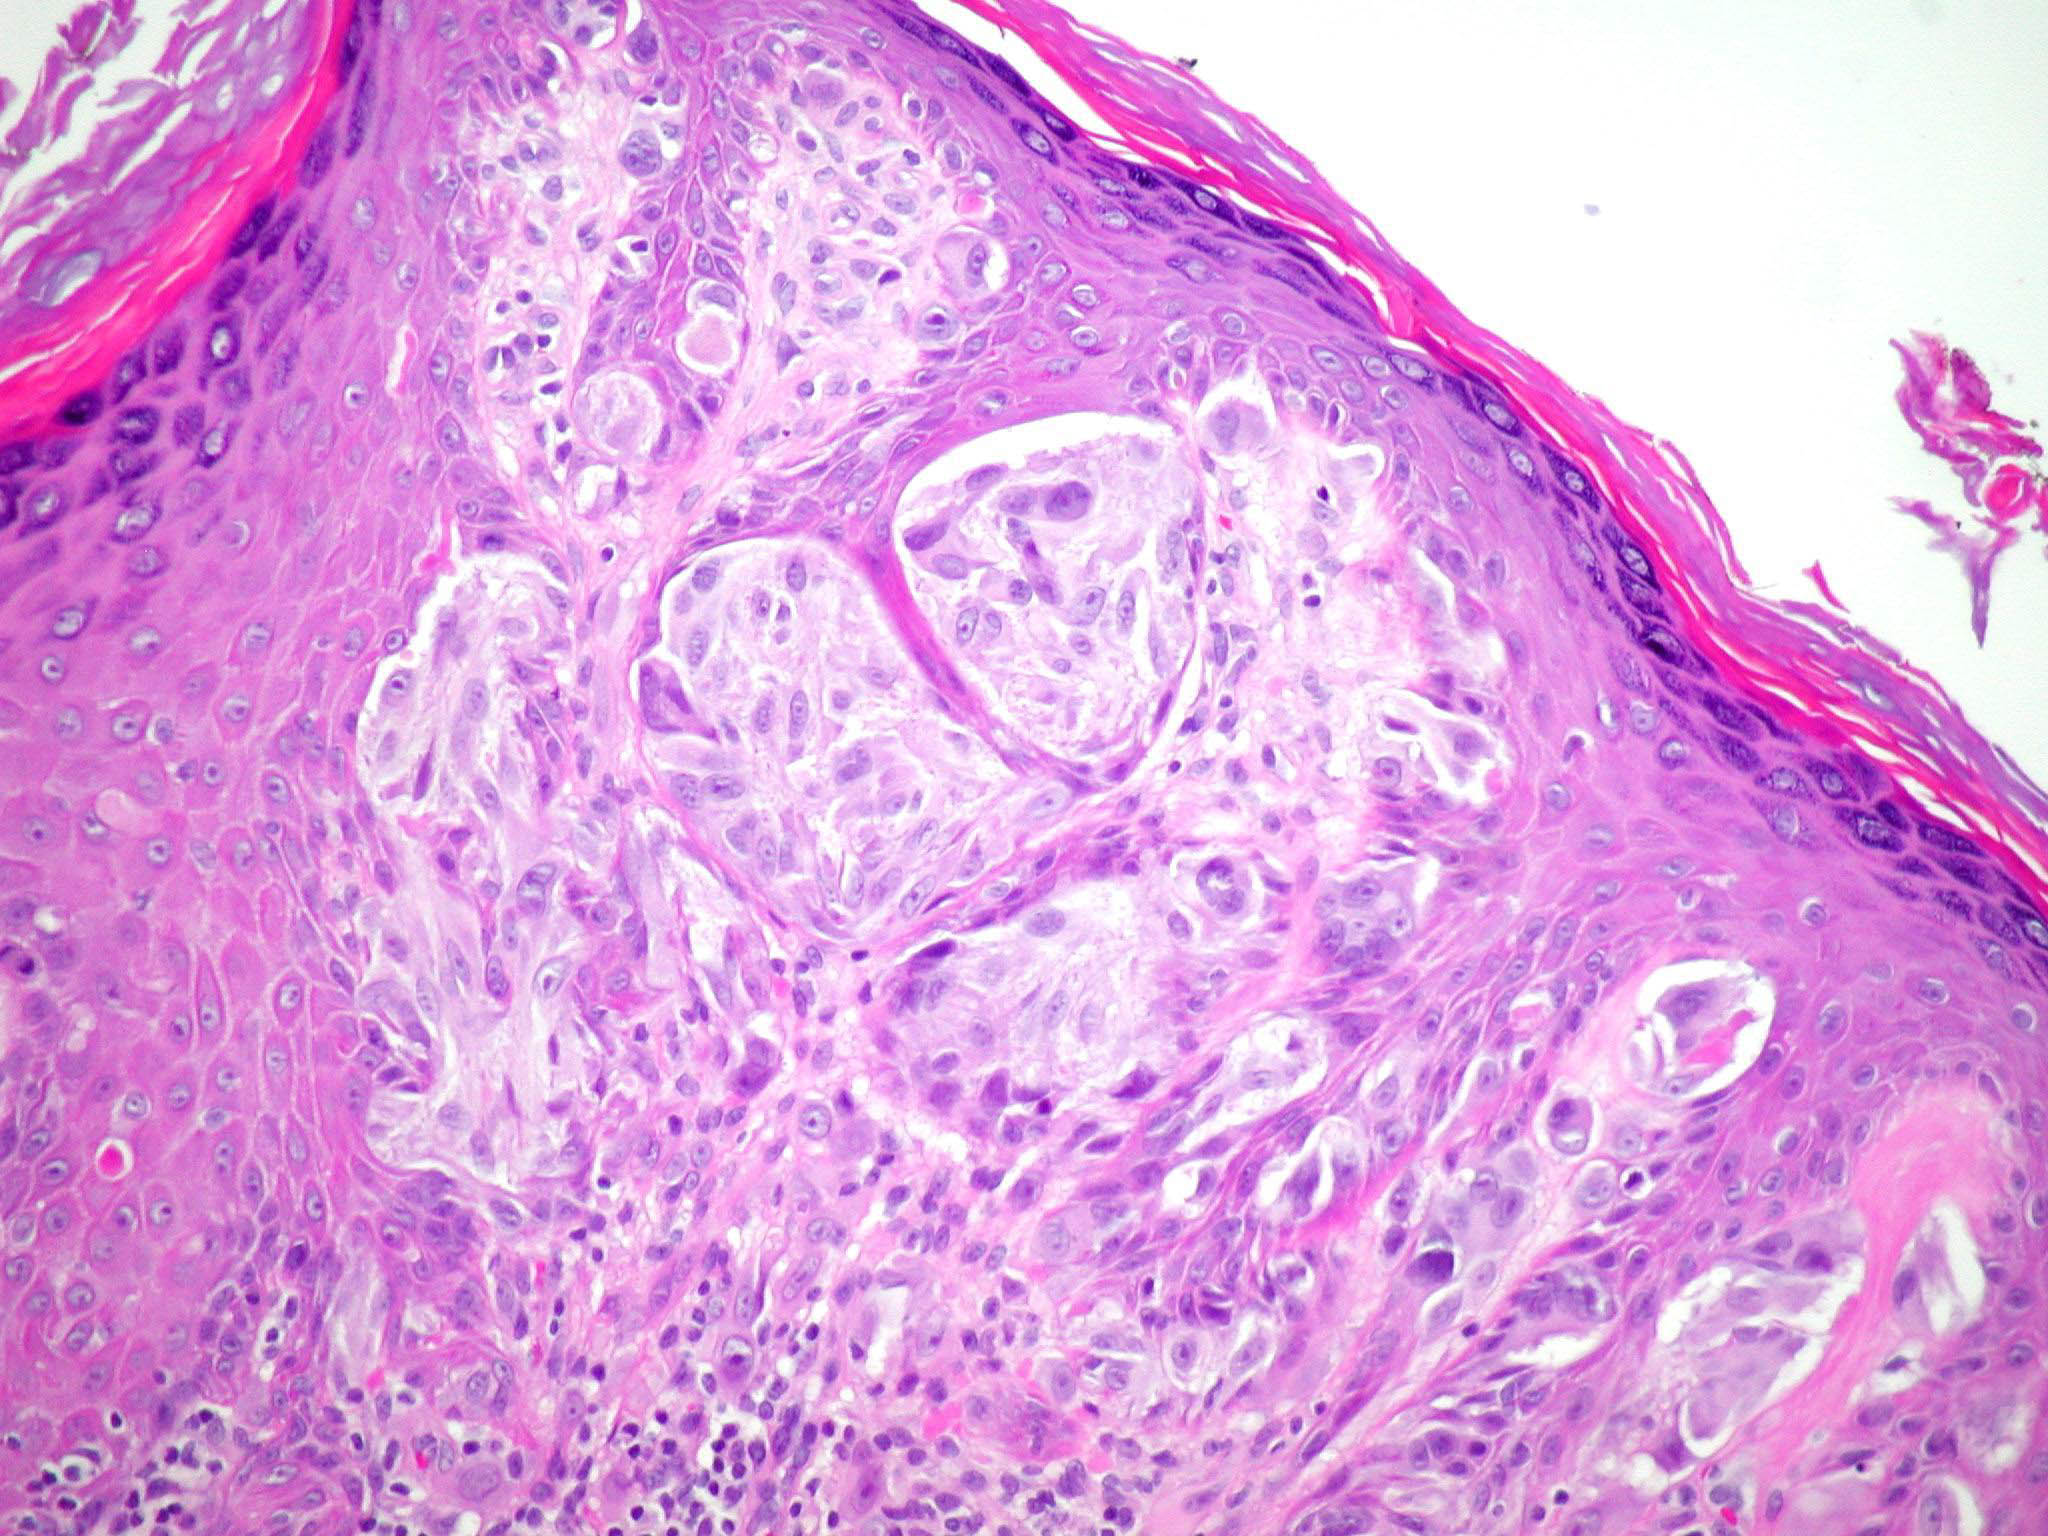

Spitz naevus (juvenile melanoma) = وحمة سبيتز _الميلانوم الفتوي